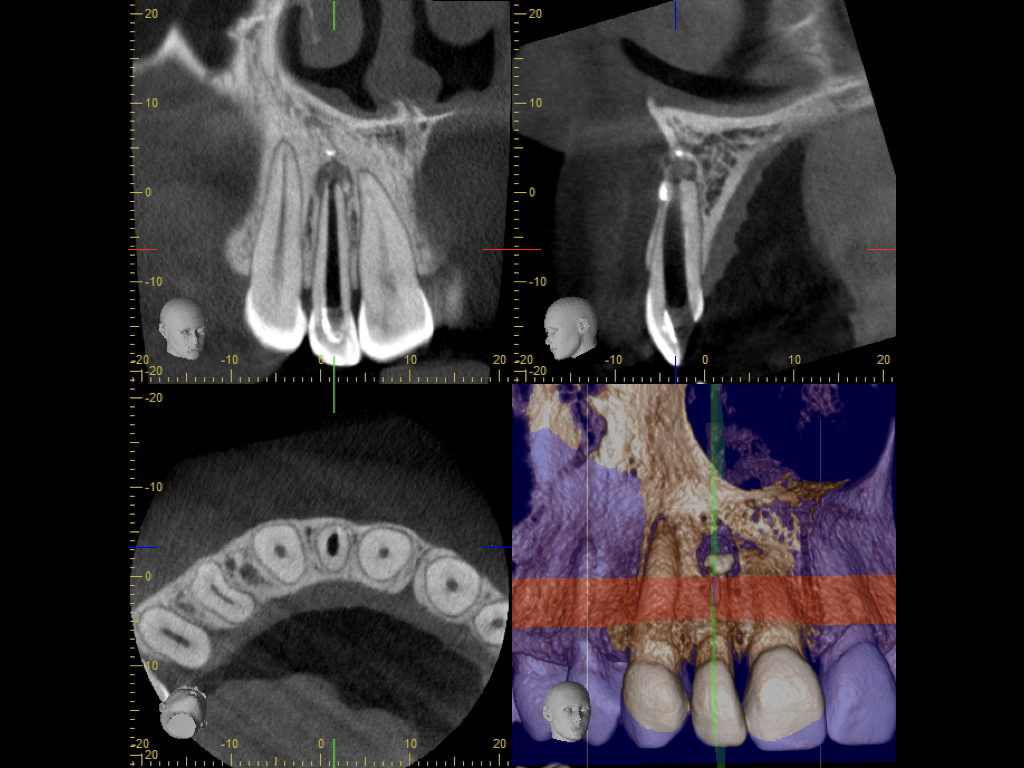

Die Revision der Revision…